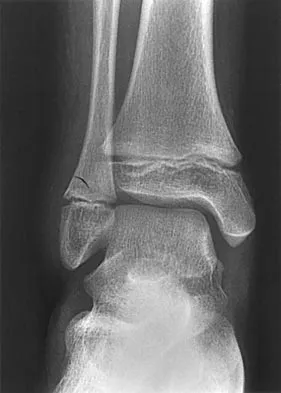

Question 48High Yield

An 11-year-old boy has had a fever and pain and swelling over the lateral aspect of his right ankle for the past 3 days. Examination reveals warmth, swelling, and tenderness over the lateral malleolus, and he has a temperature of 103.2 degrees F (39.5 degrees C). Laboratory studies show a WBC count of 13,200/mm3 with 61% neutrophils, an erythocyte sedimentation rate of 112 mm/h, and a C-reactive protein of 15.7. Radiographs and a T2-weighted MRI scan are shown in Figures 13a through 13c. Aspiration yields 1 mL of purulent fluid. Management should now consist of

Explanation

The initial signs and symptoms of acute hematogenous osteomyelitis vary widely but usually include fever, bone pain, and impaired use of the involved extremity. In lower extremity infections, the child may limp or refuse to walk. Examination often reveals bone tenderness. In more advanced cases, erythema, warmth, and swelling may be present. The WBC and neutrophil counts are not always elevated, but the erythocyte sedimentation rate will be abnormal in more than 90% of patients. When the infection is diagnosed early, before a subperiosteal abscess has formed, antibiotics alone may be adequate to treat the infection. This patient has a more advanced infection, however, with the MRI scan revealing a subperiosteal abscess that was confirmed by aspiration. When an abscess is present, surgical drainage is generally indicated to remove devitalized tissue and to enhance the efficacy of the antibiotics. Further studies, such as bone or indium scans, are not necessary and will delay definitive treatment. Scott RJ, Christofersen MR, Robertson WW Jr, et al: Acute osteomyelitis in children: A review of 116 cases. J Pediatr Orthop 1990;10:649-652.